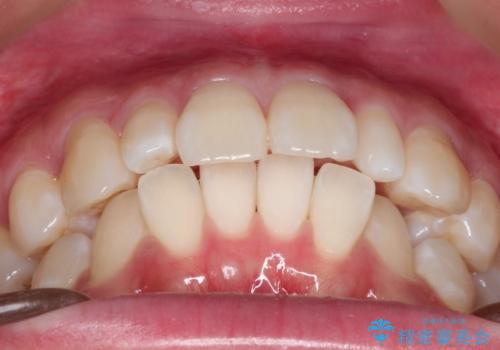

ワイヤー矯正とオールセラミックの組み合わせ治療

- 出っ歯と全体をきれいにしたいとのことで来院されました。

上顎の歯が全体的に前方に位置しているのと、前から2番目の歯が通常よりも小さい矮小歯という状態でした。

出っ歯をなおすために上顎の前から4番目の歯を抜歯して、引っ込めるのと、前から2番目の歯に通常の大きさのオールセラミックを装着して整った歯並びにすることにしました。

歯の大きさが通常と異なる場合は矯正治療で歯並びだけきれいにしても、整わないことがあります。

その場合はセラミックのかぶせ物を装着して歯の形を正常にすることで、さらに整った歯並びにすることができます。